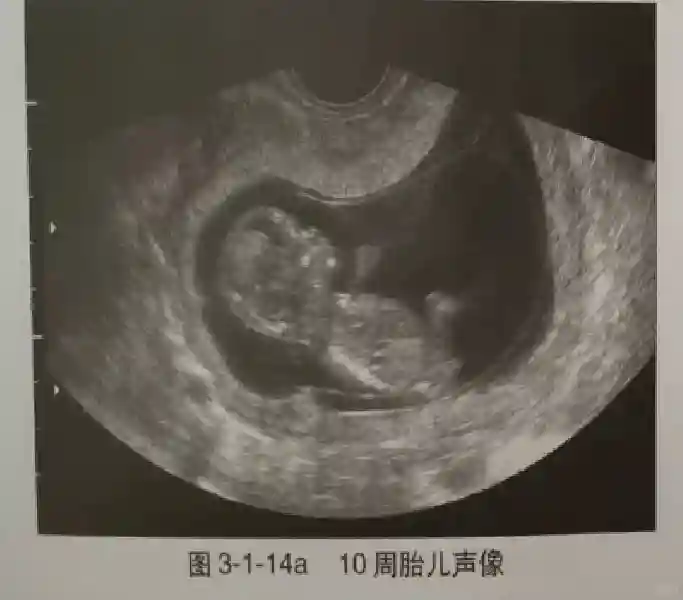

早孕早期建議采用陰道超聲檢查,以便早期了解胚胎發(fā)育情況,發(fā)現(xiàn)異常妊娠。早孕期超聲是指從證實(shí)宮內(nèi)妊娠到妊娠13+6周期間超聲觀(guān)察妊娠的情況,10周以前為胚胎,10周后為胎兒。

3??胚胎:胚胎通常在6-7周時(shí)可以為超聲顯示,起初為胎芽,表現(xiàn)為卵黃囊一側(cè)局部組織增厚,達(dá)到1 -2 mm 時(shí)才有可能為超聲測(cè)量出來(lái)。達(dá)4-5mm時(shí)可見(jiàn)胎心搏動(dòng),相應(yīng)孕周為6-6.5周,妊娠囊大小為13-18mm。胚芽長(zhǎng)度≥7㎜時(shí)仍未見(jiàn)心管搏動(dòng),提示胚胎停止發(fā)育。胚胎的出現(xiàn)和妊娠囊直徑的關(guān)系:妊娠囊直徑> 16 mm 時(shí),經(jīng)陰道超聲應(yīng)顯示胚胎。妊娠囊直徑> 25 mm 時(shí),經(jīng)腹超聲均應(yīng)顯示胚胎。